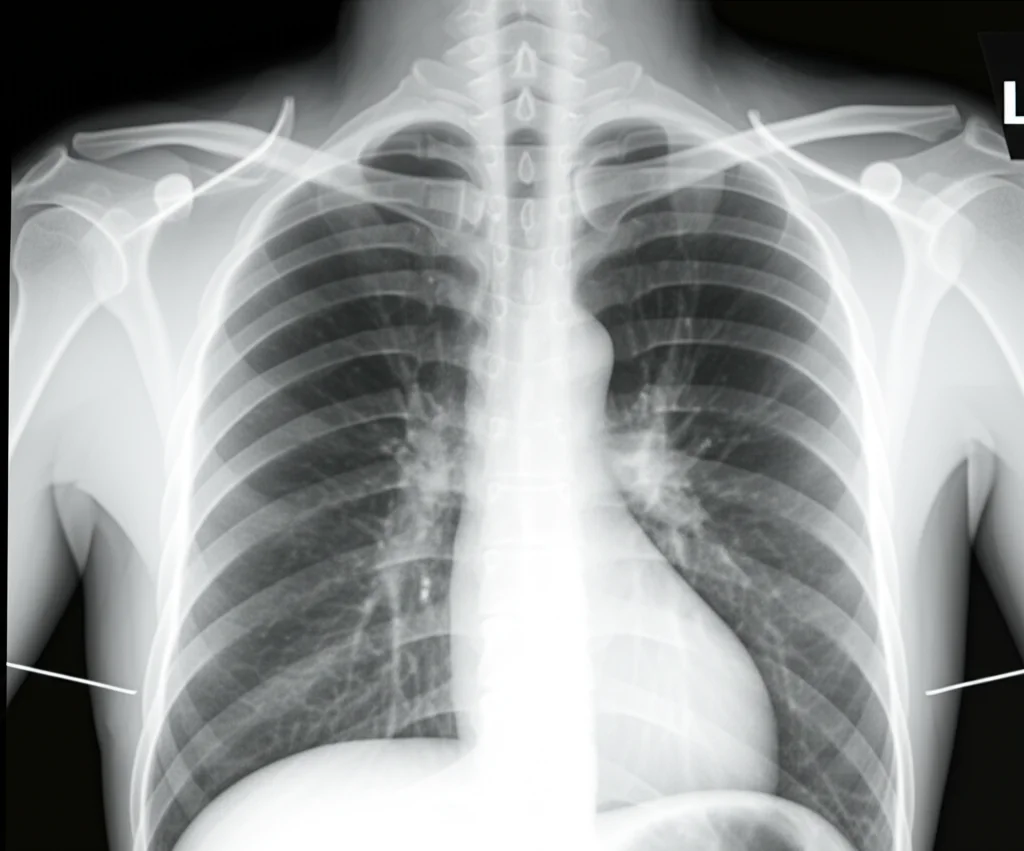

Perché è così importante? Perché ci permette di “vedere” cosa non funziona. Magari l’aria arriva bene in una zona, ma lì non c’è abbastanza flusso sanguigno per catturare l’ossigeno, o viceversa. Tradizionalmente, ci si basa su esami come radiografie, TAC e analisi del sangue, interpretando i dati con la nostra esperienza clinica. L’EIT aggiunge un livello di dettaglio incredibile, visualizzando in tempo reale le dinamiche respiratorie. È come avere una finestra aperta sui polmoni del paziente, permettendoci di personalizzare le terapie in modo molto più preciso. Ad esempio, l’EIT è già usata per ottimizzare la pressione positiva di fine espirazione (PEEP) nel ventilatore o per gestire la ventilazione a polmone singolo durante certi interventi chirurgici.

Di fronte all’ipossiemia persistente della nostra paziente, e con i dati dell’EIT che mostravano una distribuzione non uniforme della ventilazione (il centro della ventilazione era spostato verso la parte dorsale), abbiamo deciso di provare la posizione prona. Mettere il paziente a pancia in giù è una strategia ben nota e validata per la sindrome da distress respiratorio acuto (ARDS), perché sfrutta la gravità per migliorare la distribuzione della ventilazione e del flusso sanguigno, specialmente nelle zone posteriori dei polmoni che spesso collassano in posizione supina. Inoltre, aiuta a drenare le secrezioni.

Abbiamo quindi girato la paziente, monitorando costantemente con l’EIT. La prima sessione è durata 22 ore. E i risultati? L’ossigenazione è migliorata durante la pronazione! L’EIT ha confermato che la distribuzione del volume corrente era più omogenea. Tuttavia, c’era ancora un problema: il rapporto tra ventilazione e perfusione (il famoso V/Q mismatch) non era ottimale. E, cosa frustrante, appena riportavamo la paziente in posizione supina, l’ossigenazione peggiorava di nuovo. La posizione prona aiutava, ma non era la soluzione definitiva. L’EIT ci diceva che, sebbene la ventilazione fosse migliorata, la perfusione in quelle aree non era ancora adeguata.